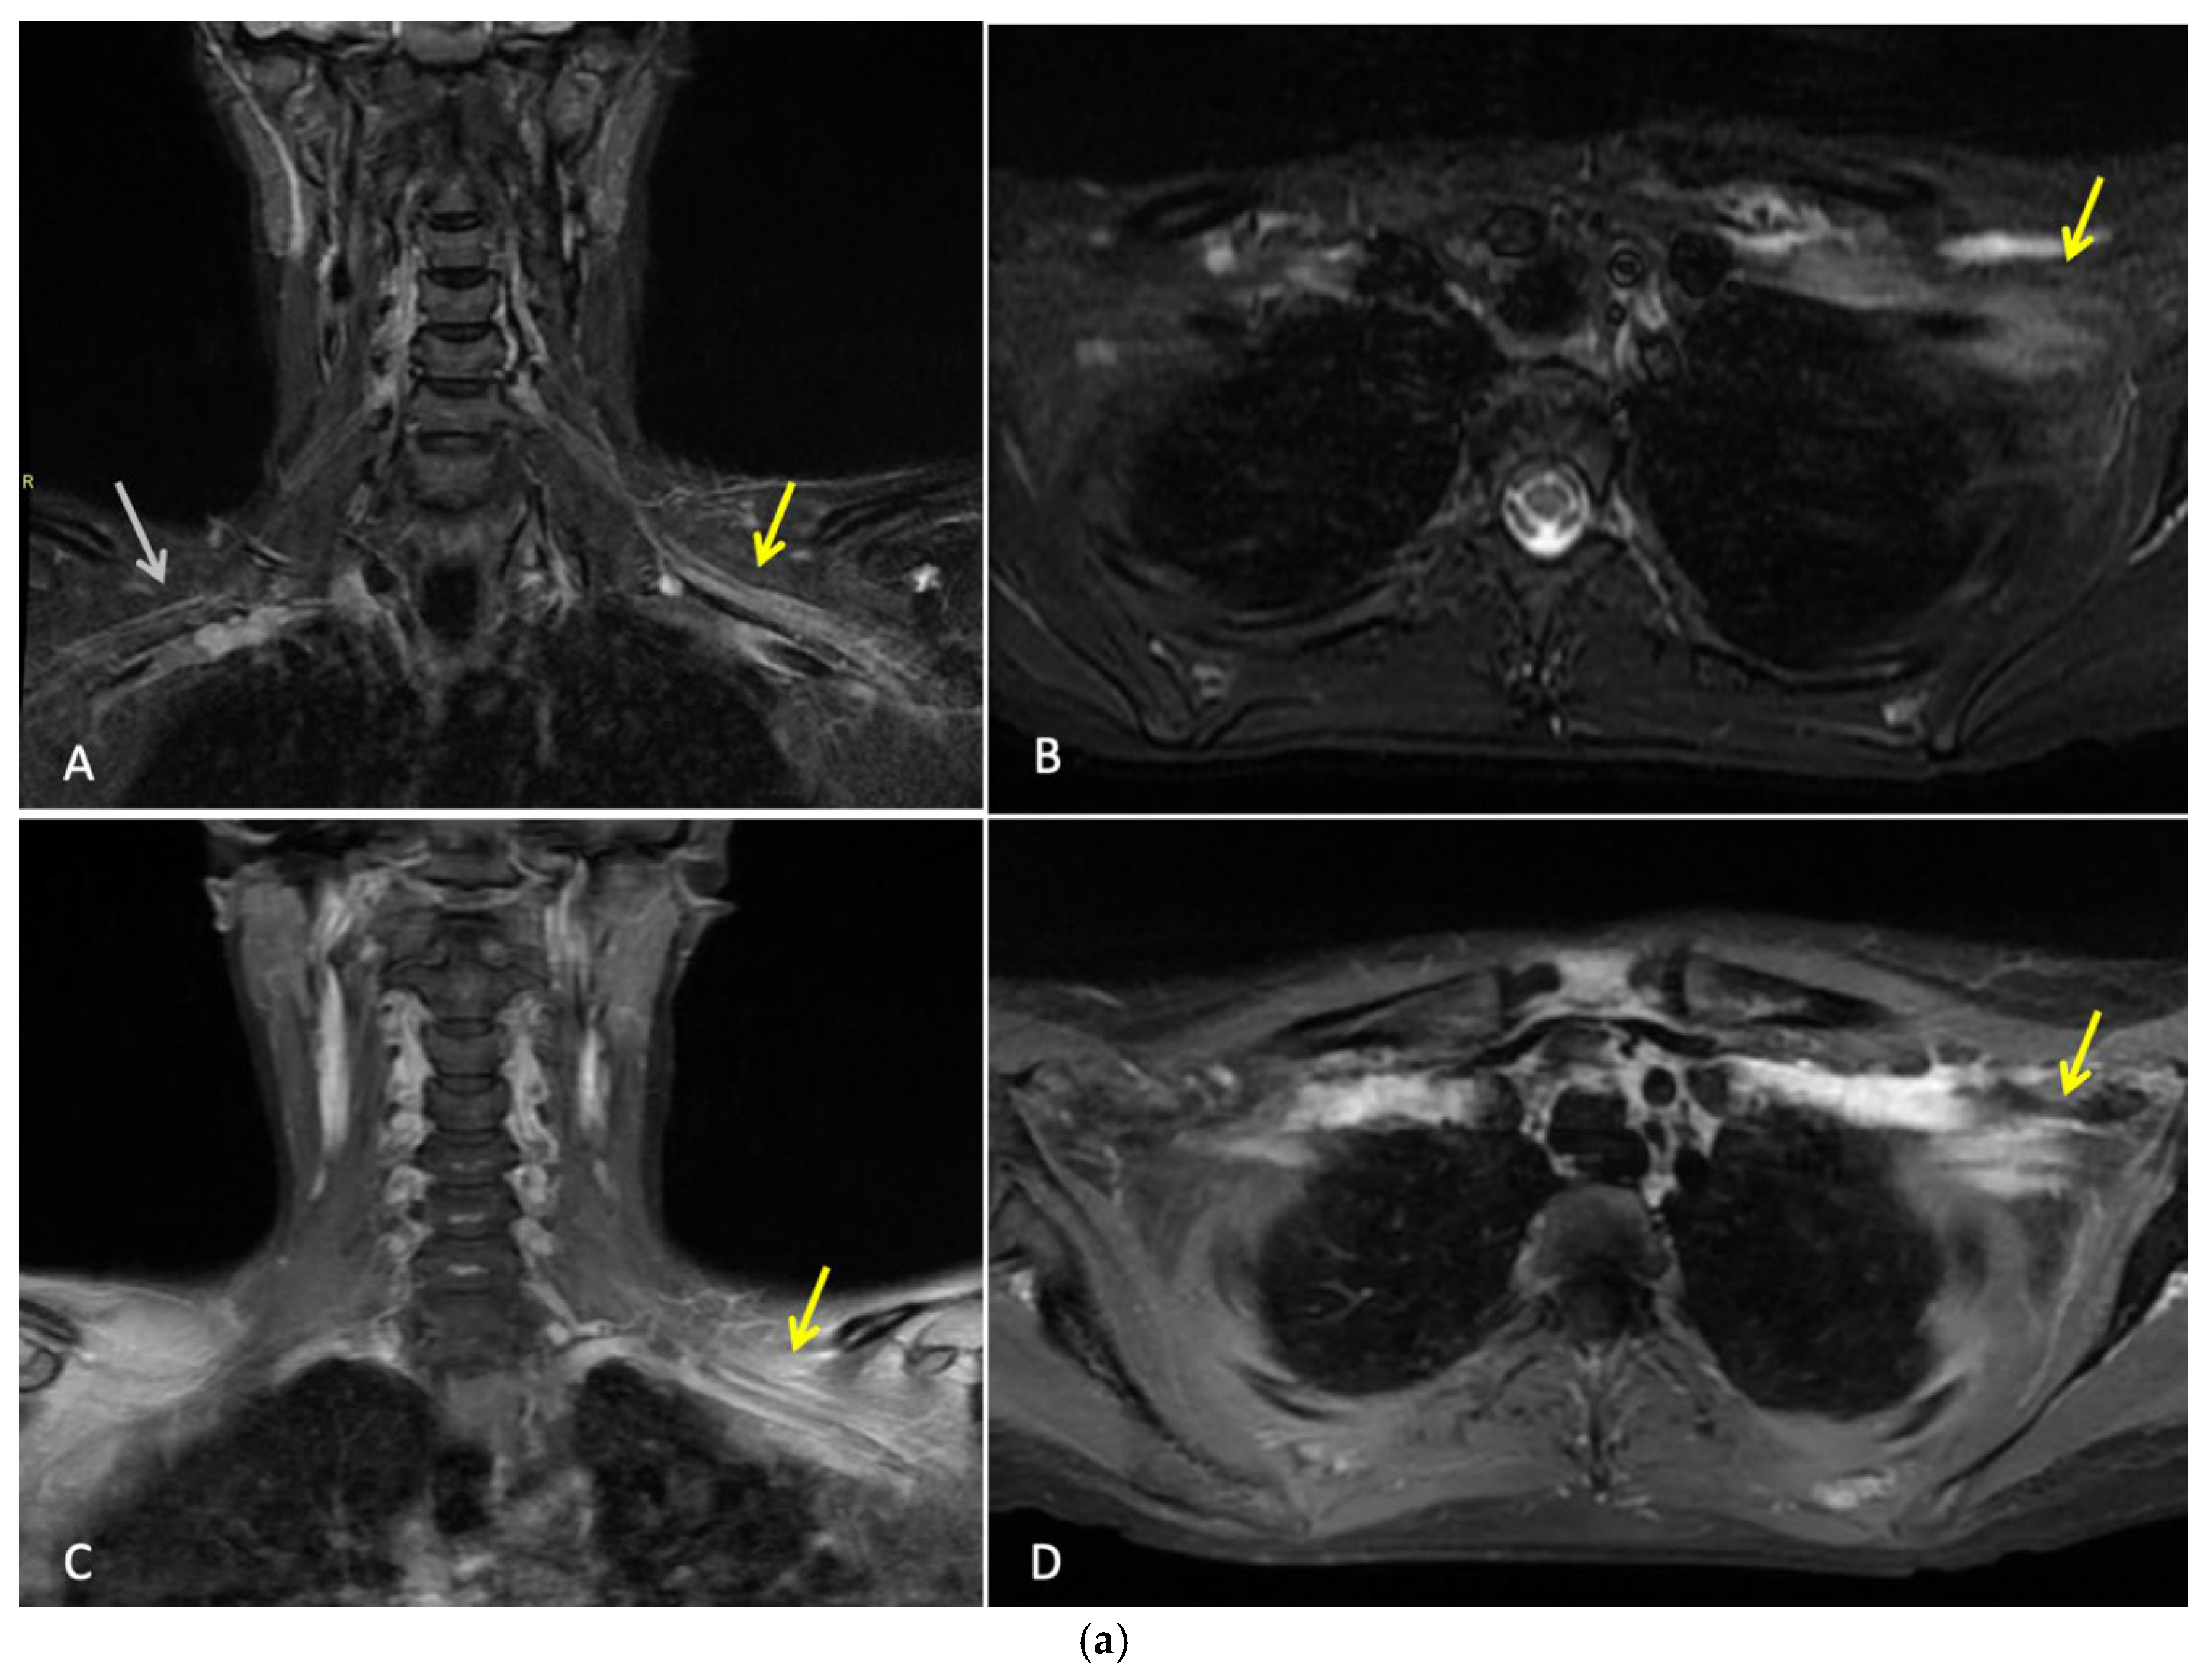

Three months after completing radiotherapy, she developed progressive numbness, paraesthesia, and weakness of the left hand. Examination revealed wasting of the thenar and hypothenar eminences, reduced grip strength, and patchy sensory loss in a C8/T1 distribution. Due to residual cancer burden after surgery, a local recurrence was initially suspected. MRI of the cervical spine and brachial plexus [Figure 2a] did not demonstrate metastatic disease, but findings were consistent with brachial plexitis. No recurrent disease was identified on PET-CT but asymmetric low grade uptake in the left brachial plexus was also consistent with brachial plexitis [Figure 2b] confirmed absence of malignancy. Electromyography (EMG) [Figure 3] and nerve conduction studies demonstrated denervation consistent with a lower-trunk brachial plexopathy; onconeuronal antibody serologies were negative.

Figure 2. a: MRI Brachial Plexus: This is a figure. Images A and B are coronal and axial T2 STIR images which demonstrate thickening and increased T2 signal of the brachial plexus on the left (yellow arrows). Normal size and signal of the brachial plexus on the right for comparison (white arrow). Images C and D are coronal and axial T1 fat saturated post contrast images which demonstrate abnormal hyperenhancement of the thickened brachial plexus on the left side (yellow arrows). Findings are consistent with left brachial plexitis. b. Whole Body FDG PET-CT: This is a figure. Images A and B are coronal and axial fused PET-CT images of the thorax. They demonstrate asymmetric low grade uptake in the left brachial plexus (yellow arrows) compared to the right side but there is no soft tissue mass or high grade uptake to suggest metastatic disease.